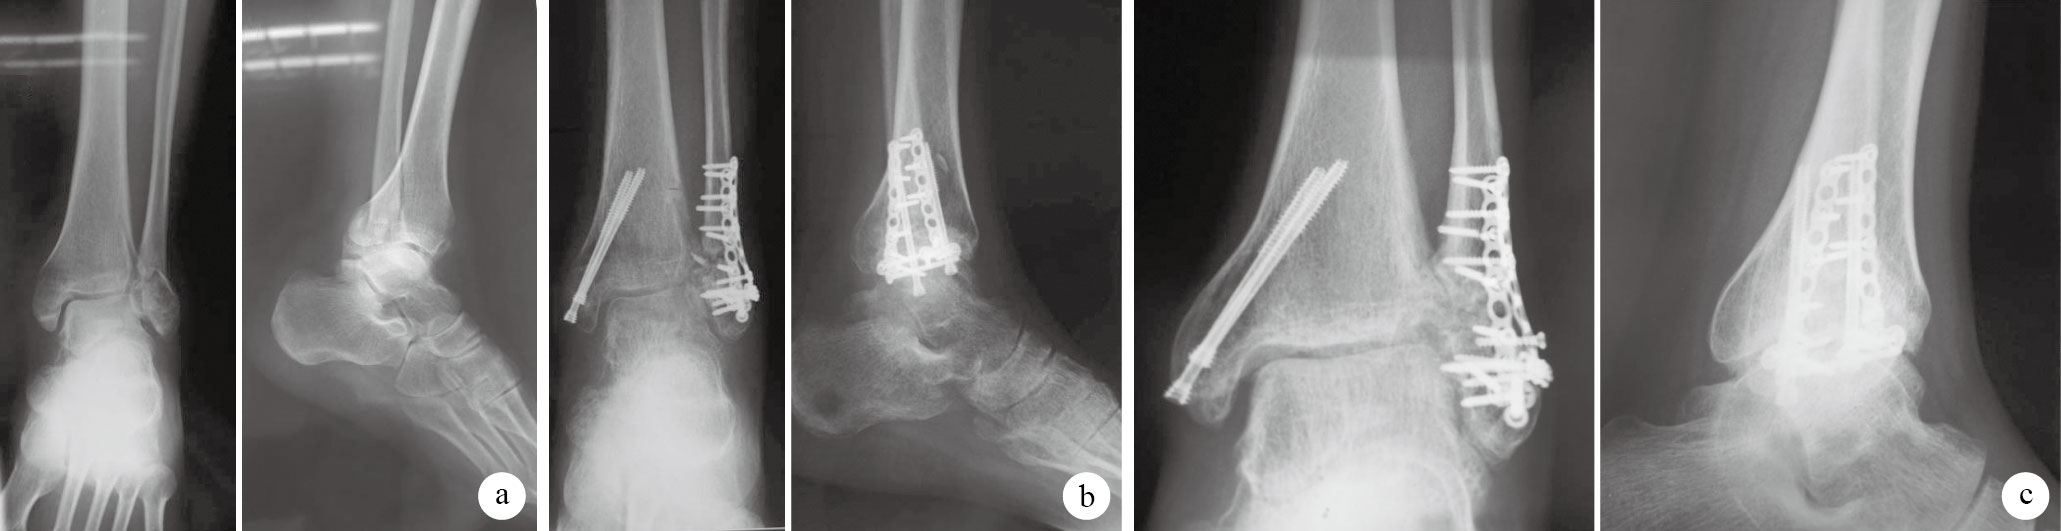

術后1例糖尿病患者切口延期愈合,經換藥后治愈;其余患者切口均Ⅰ期愈合。12例獲隨訪,隨訪時間12~24個月,平均18個月。X線片示術后10~14周骨折愈合,平均12周。隨訪期間未見內固定失敗、畸形愈合、骨不連、創傷性關節炎等并發癥發生。見圖 1。末次隨訪時AOFAS踝與后足評分為(79.6 ± 6.5)分,VAS評分為(1.3 ± 1.5)分,踝關節跖屈活動度為(70.0 ± 8.0)°,背伸活動度為(84.0 ± 5.1)°。